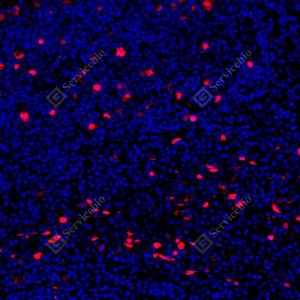

IF检测Cyclin A2蛋白(货号 GB121228)(红色). 样品: 人乳腺癌, 4%多聚甲醛 (货号G1101) 固定12-24小时. 抗原修复: 柠檬酸抗原修复液(干粉, pH 6.0) (G1201), 高压锅均匀喷气计时2分钟. 封闭: 3% BSA(货号GC305010)的PBS溶液, 室温孵育30分钟. —抗: 1: 500稀释, 4℃ 孵育过夜. 二抗: Cy3标记山羊抗小鼠IgG (H+L) (货号GB21301), 1: 300稀释, 室温孵育1小时. |

IF检测Cyclin A2蛋白(货号 GB121228)(红色). 样品: 人结肠癌, 4%多聚甲醛 (货号G1101) 固定12-24小时. 抗原修复: 柠檬酸抗原修复液(干粉, pH 6.0) (G1201), 高压锅均匀喷气计时2分钟. 封闭: 3% BSA(货号GC305010)的PBS溶液, 室温孵育30分钟. —抗: 1: 500稀释, 4℃ 孵育过夜. 二抗: Cy3标记山羊抗小鼠IgG (H+L) (货号GB21301), 1: 300稀释, 室温孵育1小时. |

IF检测Cyclin A2蛋白(货号 GB121228)(红色). 样品: 人卵巢癌, 4%多聚甲醛 (货号G1101) 固定12-24小时. 抗原修复: 柠檬酸抗原修复液(干粉, pH 6.0) (G1201), 高压锅均匀喷气计时2分钟. 封闭: 3% BSA(货号GC305010)的PBS溶液, 室温孵育30分钟. —抗: 1: 500稀释, 4℃ 孵育过夜. 二抗: Cy3标记山羊抗小鼠IgG (H+L) (货号GB21301), 1: 300稀释, 室温孵育1小时. |

IF检测Cyclin A2蛋白(货号 GB121228)(红色). 样品: 人扁桃体, 4%多聚甲醛 (货号G1101) 固定12-24小时. 抗原修复: 柠檬酸抗原修复液(干粉, pH 6.0) (G1201), 高压锅均匀喷气计时2分钟. 封闭: 3% BSA(货号GC305010)的PBS溶液, 室温孵育30分钟. —抗: 1: 500稀释, 4℃ 孵育过夜. 二抗: Cy3标记山羊抗小鼠IgG (H+L) (货号GB21301), 1: 300稀释, 室温孵育1小时. |